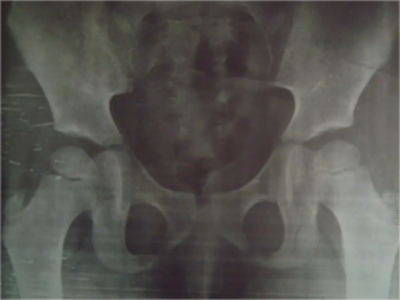

轻度隐性脊柱裂的图

隐性脊柱裂X线表现为在椎弓中央可见细微的透亮裂隙影,患者可出现轻度肌肉萎缩、麻木、遗尿以及腰痛或腿痛,多为一侧下肢受累。